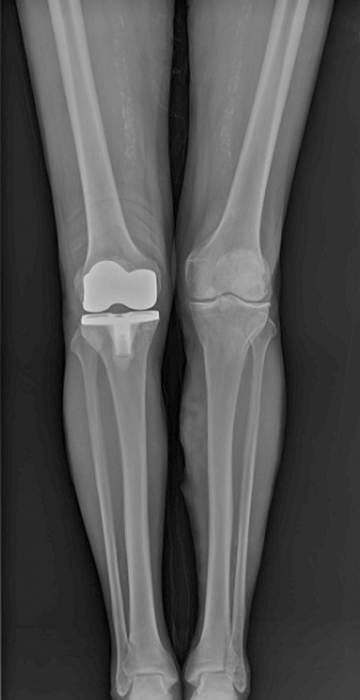

무릎인공관절 부분치환술

수술

치료

ㆍ환자 동의를 받은 자료이며, 이미지 사진은 실물과 다를 수 있습니다.

ㆍ전 : 2020.08.04 / 후 : 2021.01.26 엑스레이 전,후 사진입니다.